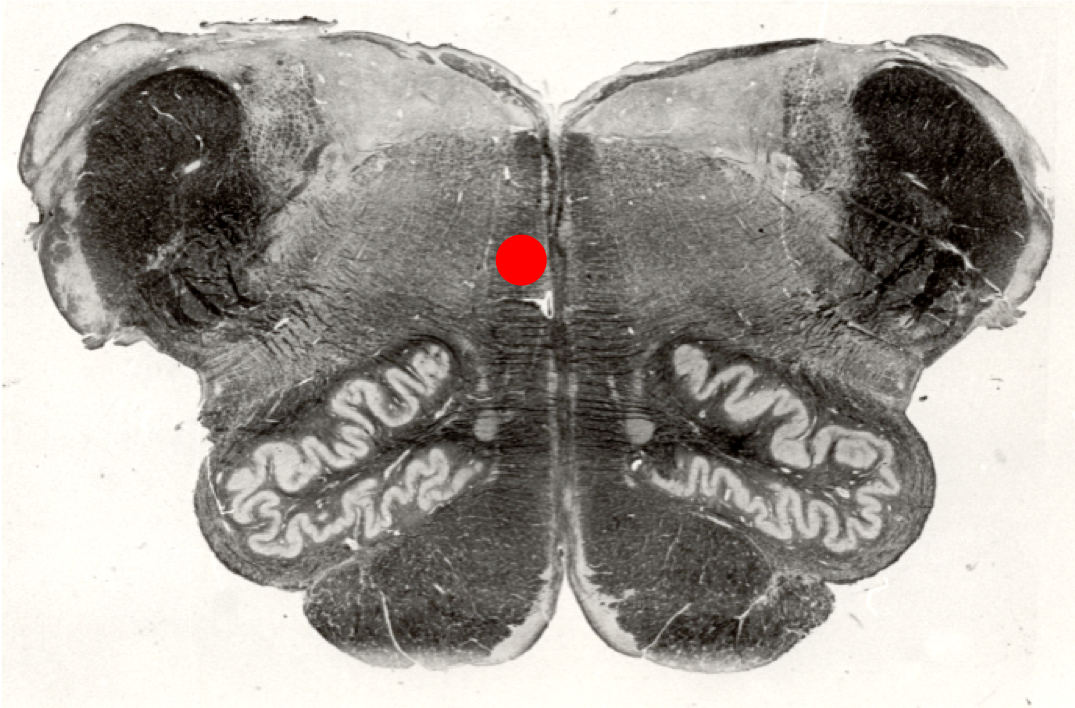

This cross section corresponds to which level of the brainstem:

level of rostral medulla

The structure indicated by the red pin contains:

Cell bodies of primary somatosensory neurons